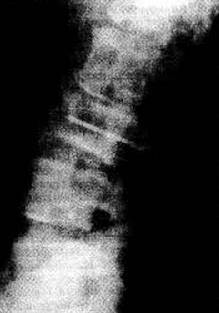

Визуализационные методы исследования для определения скелетных повреждений и параспинальных повреждений костного мозга (рентген, компьютерная или магнитно-резонансная томографии).